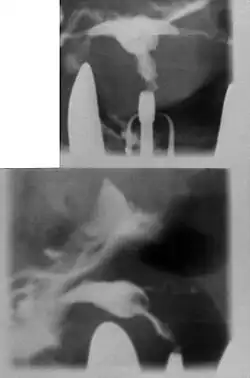

| Hysterosalpingography of a T-shaped uterus. | |

Women are often diagnosed with this condition after several failed pregnancies, proceeded by exploratory diagnostic procedures, such as magnetic resonance, sonography, and particularly hysterosalpingography.[6][7][8] In such studies, a widening of the interstitial and isthmus of uterine tube is observed, as well as constrictions or narrowing of the uterus as a whole, especially the lower and lateral portions, hence the "t" denomination. The uterus might be simultaneously reduced in volume, and other abnormalities might be concomitantly present.[9]